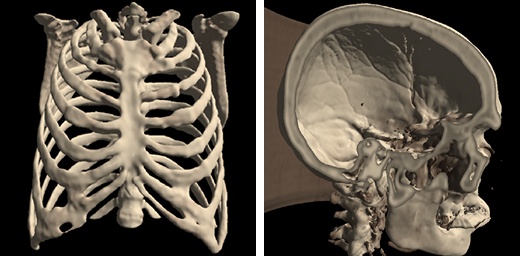

Isosurface Visualization¶

This method suits for bones, skin surface and segmented areas visualization. The base of this method is a search of intersection points between the rays corresponding to pixels and the isosurface. The user selects the level of the isosurface and the clipping plane position with sliders.